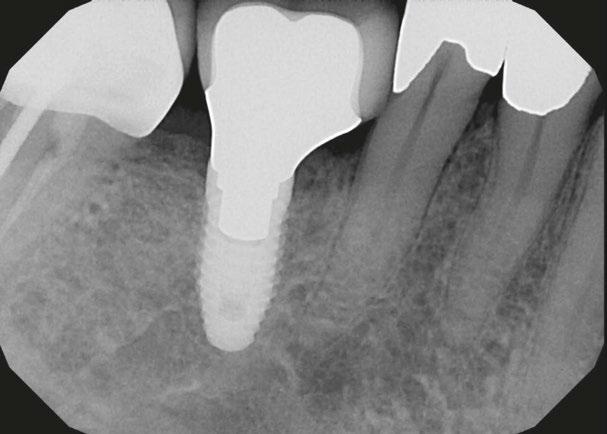

Figure 3: Second maxillary molar with external root resorption (ERR) with incidentally captured ERR on the lower mandibular first molar as well. When there is one tooth with resorption, be suspicious of other teeth with resorption, especially on younger patients Figure 6: No PARL on PA film. Clear PARL on scan taken with medicament Figures 4 and 5: 4. Mandibular molar with a J-shaped lesion due to endo — not a vertical root fracture. Path of least resistance happens to be through a distal perio pocket, but this is an endo-perio lesion and not a VRF. Incidentally, a mucous retention cyst was captured in the sinus. 5. Healing after bridge removal and retreatment

a realistic prognosis. Unfortunately, not all teeth can be saved. Some are not candidates for retreatment (Figure 11). Without a CBCT scan, it would be easy to attempt these retreatments only to discover the true problem mid-treatment, or worse — to think I had caused one (Figures 10 and 11). This added information not only helps the practitioner, but also provides patients a higher level of confidence and trust in you.

With retreatments, maybe the root canal looks completely fine on a PA or panoramic x-ray, but the patient says that it just doesn’t feel right. A cone beam can often reveal the cause of the patient’s discomfort. This could be that the tooth was perforated, cracked or has an unfilled canal, and the patient is totally justified in feeling like something’s wrong. Or sometimes the scan will show that there is another issue on an adjacent tooth or in the patient’s sinuses (causing their discomfort). When patients sense a problem but are told that there is not one (usually based on 2D radiographs), that’s not a great feeling. Being able to show the patient the CBCT scan and say, “You were right, and here’s the issue,” improves the patient experience.

I also see a good amount of resorption cases. Without the scan, I can’t determine how large or destructive the lesion is. I cannot accurately determine the best course for these resorptive cases without knowing what they look like in 3D (Figure 3). I might approach it surgically without endo, or I might plan only for the endo and monitor it after. And, some cases need both at

I’m also changing my treatment plans based on the data from my CBCT. Sometimes I look at a root canal treated PA and presume I know what I will do: a retreatment or an apico. Another recent, poignant case: a lower incisor with a previous RCT and a previous apico (Figure 9). Usually, once a tooth has had an apico, there may not be much left to offer and most of the time, the default is another apico, especially as there was very little room for an implant on the lower anteriors. I scanned the tooth and saw that a whole canal had been missed — twice! The RCT and the apico had left the buccal canal completely untouched. I changed my treatment plan based on this information!